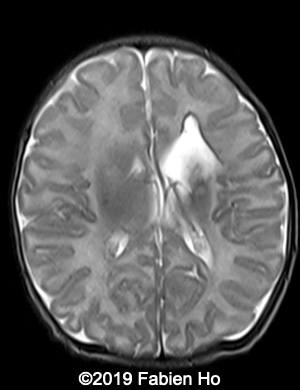

Images 12-16: we performed a second fetal brain MRI at 32 weeks, which showed the same findings as the postnatal neonatal brain MRI as follows:

The evolution of the images is typical of a clastic lesion: after resorption of the ischemic tissue and hematoma, there was now a focal porencephaly with hemosiderin tattooing on its margins. Conversely, persistence of the same MRI findings would have indicated an hypercellular brain tumor, which could have been a differential diagnosis.